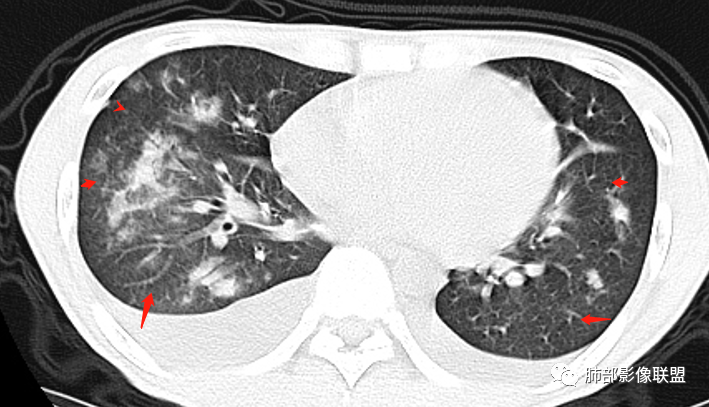

丽:青年男性,双下肢水肿,病史无肺部症状,化验白细胞明显减低;白蛋白低,提示双侧胸腔积液可能低蛋白所致。补体值降低提示自身免疫性疾病,影像见双肺散在结节样,斑片状高密度影及实变密度影,大部分沿支气管血管束分布,以右肺下叶为主,内可见充气支气管征,周围可见磨玻璃密度,并见多发小叶间隔增厚,伴心包少许积液,双肺病变,临床无症状,感染首先除外,结合腮腺病变,双下肢病变及化验检查,综合考虑自身免疫性疾病肺部改变

红星:病史资料:患者男,30岁,因“双小腿及双踝双足浮肿1周”入院。患者1周前无明显诱因下感双小腿及双踝双足浮肿,胸部CT示:两肺多发感染。尿酸增高,肝功能损害,两肺多发的结节状及片状的模糊阴影,小叶中心分布为主,病灶中心密度比较高,周围密度较淡,晕征,整体病灶比较单一,以渗出为主,两下肺分布,尤其是右下肺分布为甚,两侧胸腔积液,心包积液。心脏左心室明显增大。考虑肺部感染或者是血管炎的一些病变。个人认为,左心功能不全合并有肺水肿或者是血管炎的一些病变。

一切∮随缘:右肺多发大片状实变影,边界模糊,周围可见磨玻璃影,部分可见支气管穿行,支气管壁增厚,支气管扩张,血管束增粗,双肺多发结节,结节分布,以支气管束分布为主,双侧胸腔积液,心包积液,心包密度减低(贫血?),年轻男性,有下肢浮肿,实验室有血象及蛋白减低,考虑:1:病毒性肺炎2:GPA3:淋巴瘤

张延军:双肺多发斑片及结节状高密度影,边缘不清,结节周围伴晕征,前者沿支气管束分布呈实变影,内走形支气管通畅,临近肺组织见大片状磨玻璃影,界不清,中轴间质增厚,影像提示,支气管血管束周围及肺内间质为主病变,临床风免提示,考虑结蹄组织疾病肺内改变

双侧胸腔积液,双下肺斑片状磨玻璃密度影,背景是大片状磨玻璃密度影,密度稍低一些。这个磨玻璃影非常弥漫,没有受局限,胸膜下不是很清楚,内部结构显示清楚,稍实变的区域也是,小叶间隔增厚,中轴间质也增厚。有些病变边缘有收缩,有轻度OP样特点,但是这些病变似乎密度非常均匀。

这类病变首先不是气道来源的,应该是沿间质分布,或者是肺泡腔内的病变。支气管壁周围增厚,磨玻璃影非常均匀,肺泡腔应该也有。

出血有可能,还要考虑到肺水肿,因为有胸腔和心包积液,小叶间隔也增厚。